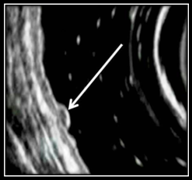

Инфильтративная форма

Визуализируется в виде гипоэхогеного образования с гетероэхогенными включениями, характеризуется инфильтративным ростом со значительным распространением опухолевой инфильтрации по подслизистому слою (рис. 6).

Рис. 6. Инфильтративная форма НЭО желудка

Анализ глубины инвазии опухоли по результатам эндосонографических исследований определил:

— плосковозвышающаяся форма в 100% распространялась в пределах слизистой оболочки стенки желудка;

— опухолевая инвазия полиповидной формы в 18,2% ограничивалась слизистым слоем, инвазия подслизистого слоя отмечена у 72,7%, в 9,1% опухоль распространялась на мышечный слой стенки желудка при размерах образования 2 и более см в диаметре;

— при инфильтративной форме в 33,3% опухоль ограничивалась поражением слизистого и подслизистого слоев стенки желудка, а в 66,7% имелась инвазия мышечного слоя и серозы.